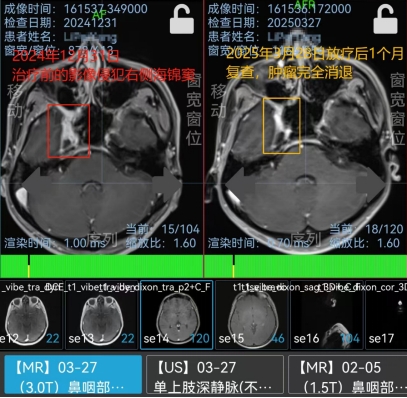

3. Kết quả điều trị: Sự biến mất hoàn toàn của khối u

Sau liệu trình 30 buổi xạ trị chính xác , kết quả đạt được vô cùng ấn tượng, vượt xa kỳ vọng của gia đình bệnh nhân:

Xóa cửa sổ phát nguyên khối u: Hình ảnh nội dung và CT kiểm tra xem khối u được tìm thấy ở phân vùng đã bị mất hoàn toàn .

Kiểm soát bá cháy di căn: Toàn bộ các bạch huyết vùng cổ – ngân hàng là nơi tế bào ung thư bình ẩn ẩn cũng đã được giải quyết triệt để, không còn dấu hiệu đại hay xâm lấn.